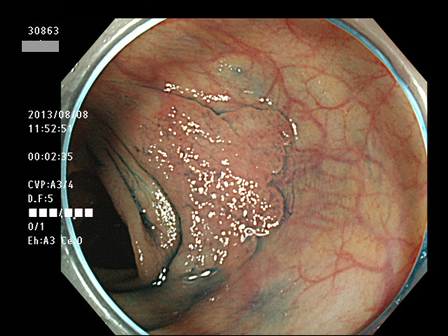

上記100名より抽出した平坦・陥凹型腺腫(=癌化の危険が高いが見落としやすい病変)の内視鏡写真

30801 30804 30805 30814 30819 30822 30823 30825 30827 30828 30829 30830 30833 30834 30835 30837 30838 30839 30840 30841 30843 30846 30848 30850 30853 30854 30855 30857 30858 30860 30862 30863 30867 30868 30870 30872 30873 30874 30875 30876 30882 30884 30886 30887 30891 30892 30893 30894 30895 30897 30898・・・・・・の52名